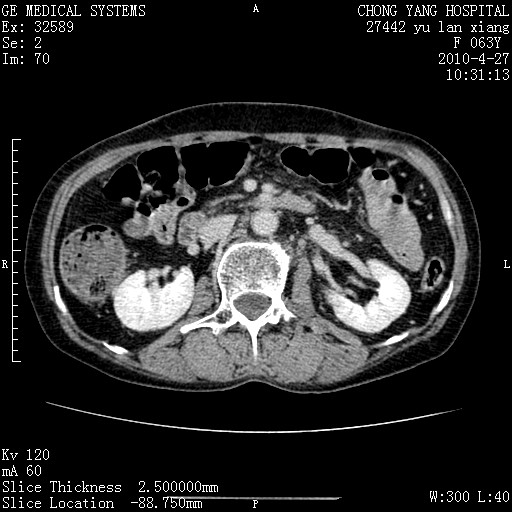

标题: CT26066:F63Y 上腹正中压痛半月,CA199:7400u/ml,MR示胰腺炎伴 [打印本页]

胰腺癌侵犯腹腔动脉干-分支、胃壁、左侧膈肌伴胰周及腹膜后淋巴结转移、胆囊切除术后。

胰腺癌侵犯腹腔动脉干-分支、胃壁、左侧膈肌伴胰周及腹膜后淋巴结转移、胆囊未显影。